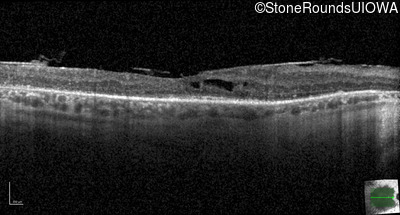

AR Retinitis Pigmentosa (IA1aiii)

Age at visit: 46 years

This 46 year old man has had poor vision in dim light since age 2.

Diagnosis & molecular findings

AR Retinitis Pigmentosa SLC24A1 Met252 del2ggaAT Leu1052 del2ctTC AR